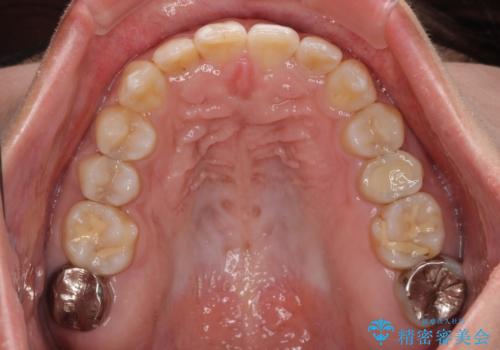

- 上下前歯の叢生を気にして来院された患者様です。

軽度な叢生であり、安価で短期間の治療を規模されていたため、インビザライン・モデレートを用いて矯正治療を行うこととしました。